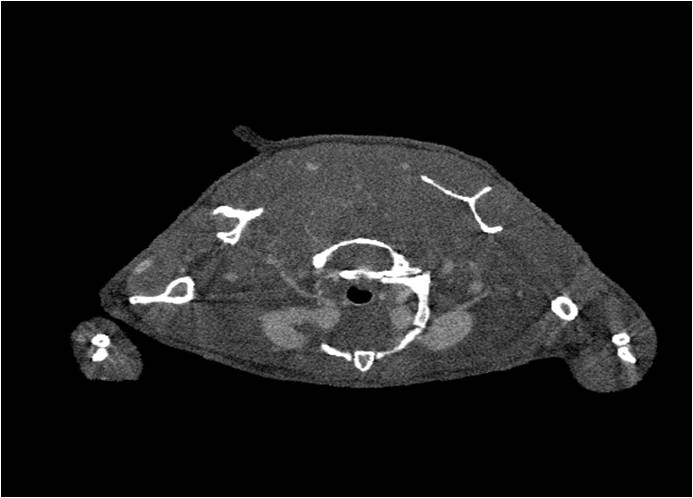

肺轉(zhuǎn)移

小鼠模式,22.5μm像素

正常

8天 14天

無(wú)造影劑注入 造影劑注入